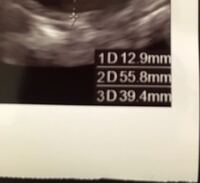

エコー写真の見方がわかりません 子宮のエコー 1d 2d Yahoo 知恵袋